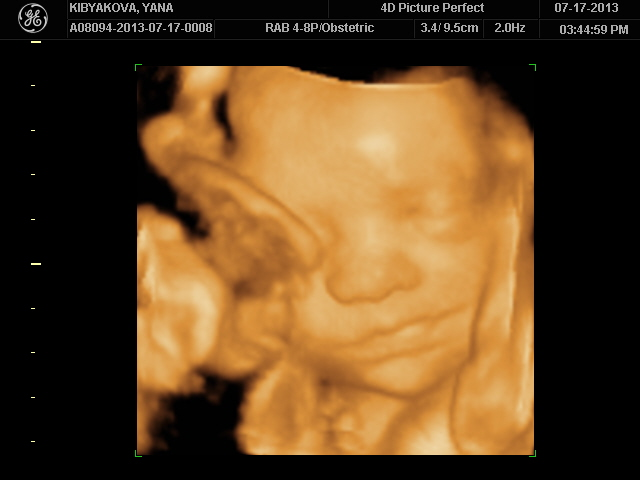

Спорили после с мужем на кого он похож!Мои родители в голос закричали что он моя копия,кроме глаз, муж говорит что нос его и верхняя губа тоже,а нижняя моя!))Я не стала ни с кем спорить просто весь день перекручиваю подробности узи)Моя кроха даже улыбаться умеет и хмуриться - это мы тоже увидели,жаль заснять не успели...В общем я со своих эмоций уже всего и не вспомню, но знаю точно что это было пока что самое лучше свидание с ним!)

И ножку показали всем!Вот какая большая у нас она))))Самое главное что муж разглядел ВСЁ(я думала придется объяснять ему что где) и так же в него влюблен ещё больше как и я!))))Я теперь вообще не отпускаю фотки эти))Постоянно смотрю своего Сашульку

Сыночек прелесть такой лапочка!)